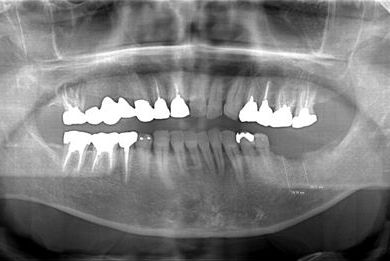

| 性別/年齢 | 男性 / 53歳 | ||||||||||||||||||||||||||||||||

| 主訴 | 左下奥歯2本のインプラント治療を希望。 | ||||||||||||||||||||||||||||||||

| 治療方針 | 左下欠損部分をインプラント治療にて機能的・審美的回復を行う。 | ||||||||||||||||||||||||||||||||

| 治療内容 | インプラント2本、ハイブリッドセラミッククラウン2本 | ||||||||||||||||||||||||||||||||

| 総治療費 | 399,000円 | ||||||||||||||||||||||||||||||||

| 治療期間 | 9ヶ月 |